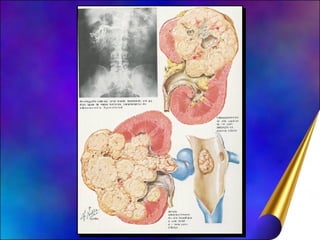

Tumor de Wilms Max Wilms, 1899, Tu renal misto Incidência:  neoplasia + frequente da infância  ( 8: 1.000.000) Ambos sexos:  pico em tôrno 3 anos (75% entre 1 e 5 anos) ; 5% dos casos é bilateral Forma esporádica ou familiar ( + precocemente e bilateral) Anomalias associadas (15%) : Genitourinárias: Criptorquidia, hipospádia,  rins  fundidos, duplicidade pieloureteral Aniridia (Lesão ocular)

Tumor de Wilms Etiologia : Restos do blastema metanefrogênico Estadiamento :  I  a  V Metástases : Localmente  (retroperitonial, veia renal, ggl. regionais); 10% para pulmão, fígado, ossos, cérebro Prognóstico: Idade paciente, extensão doença (estadiamento) Tipo histológico, ressecabilidade cirúrgica Clínica: Percepção massa abdominal ( 90% ) Dor abdominal e hematúria macroscópica ( 20%)

Tumor de WilmsMax Wilms, 1899, Tu renal misto Incidência: neoplasia + frequente da infância ( 8: 1.000.000) Ambos sexos: pico em tôrno 3 anos (75% entre 1 e 5 anos) ; 5% dos casos é bilateral Forma esporádica ou familiar ( + precocemente e bilateral) Anomalias associadas (15%) : Genitourinárias: Criptorquidia, hipospádia, rins fundidos, duplicidade pieloureteral Aniridia (Lesão ocular)

Tumor de WilmsEtiologia : Restos do blastema metanefrogênico Estadiamento : I a V Metástases : Localmente (retroperitonial, veia renal, ggl. regionais); 10% para pulmão, fígado, ossos, cérebro Prognóstico: Idade paciente, extensão doença (estadiamento) Tipo histológico, ressecabilidade cirúrgica Clínica: Percepção massa abdominal ( 90% ) Dor abdominal e hematúria macroscópica ( 20%)